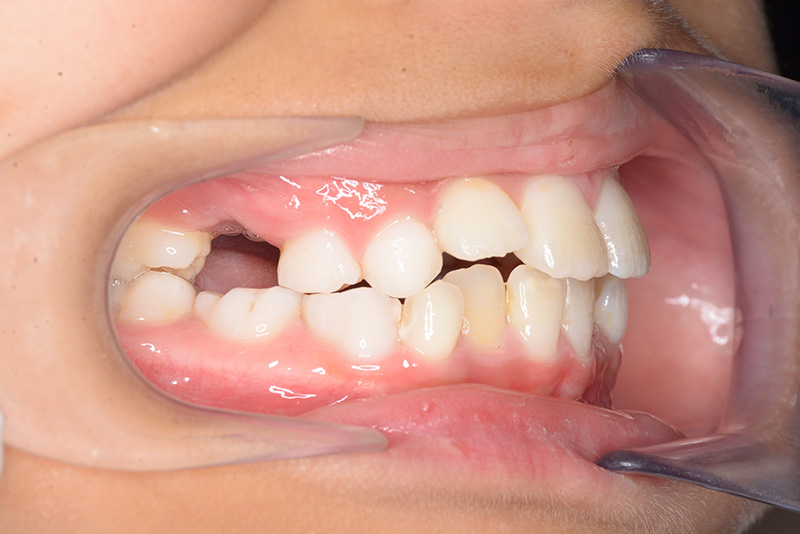

| 主訴 | 上顎6の近心傾斜、5萌出部位不足 | 診断名 | アングルⅡ級叢生症例 | ||||

|---|---|---|---|---|---|---|---|

| 初診時年齢 | 8歳9ヵ月 | 性別 | 女 | 動的治療期間 | 4ヵ月 | ||

| 顔貌所見 | 正貌はほぼ左右対称。側貌はstraight type、引き締まった口唇形態をしていた。 |

| 口腔内所見 | over jet 2.5mm、over bite 2.0mm、右側大臼歯関係はEnd on class Ⅱ、上顎左側Eは早期喪失により左側大臼歯関係はFull classⅡ、右側Eは6の異所萌出により歯根吸収が進行したため一般歯科医院にて抜去済みであった。 |